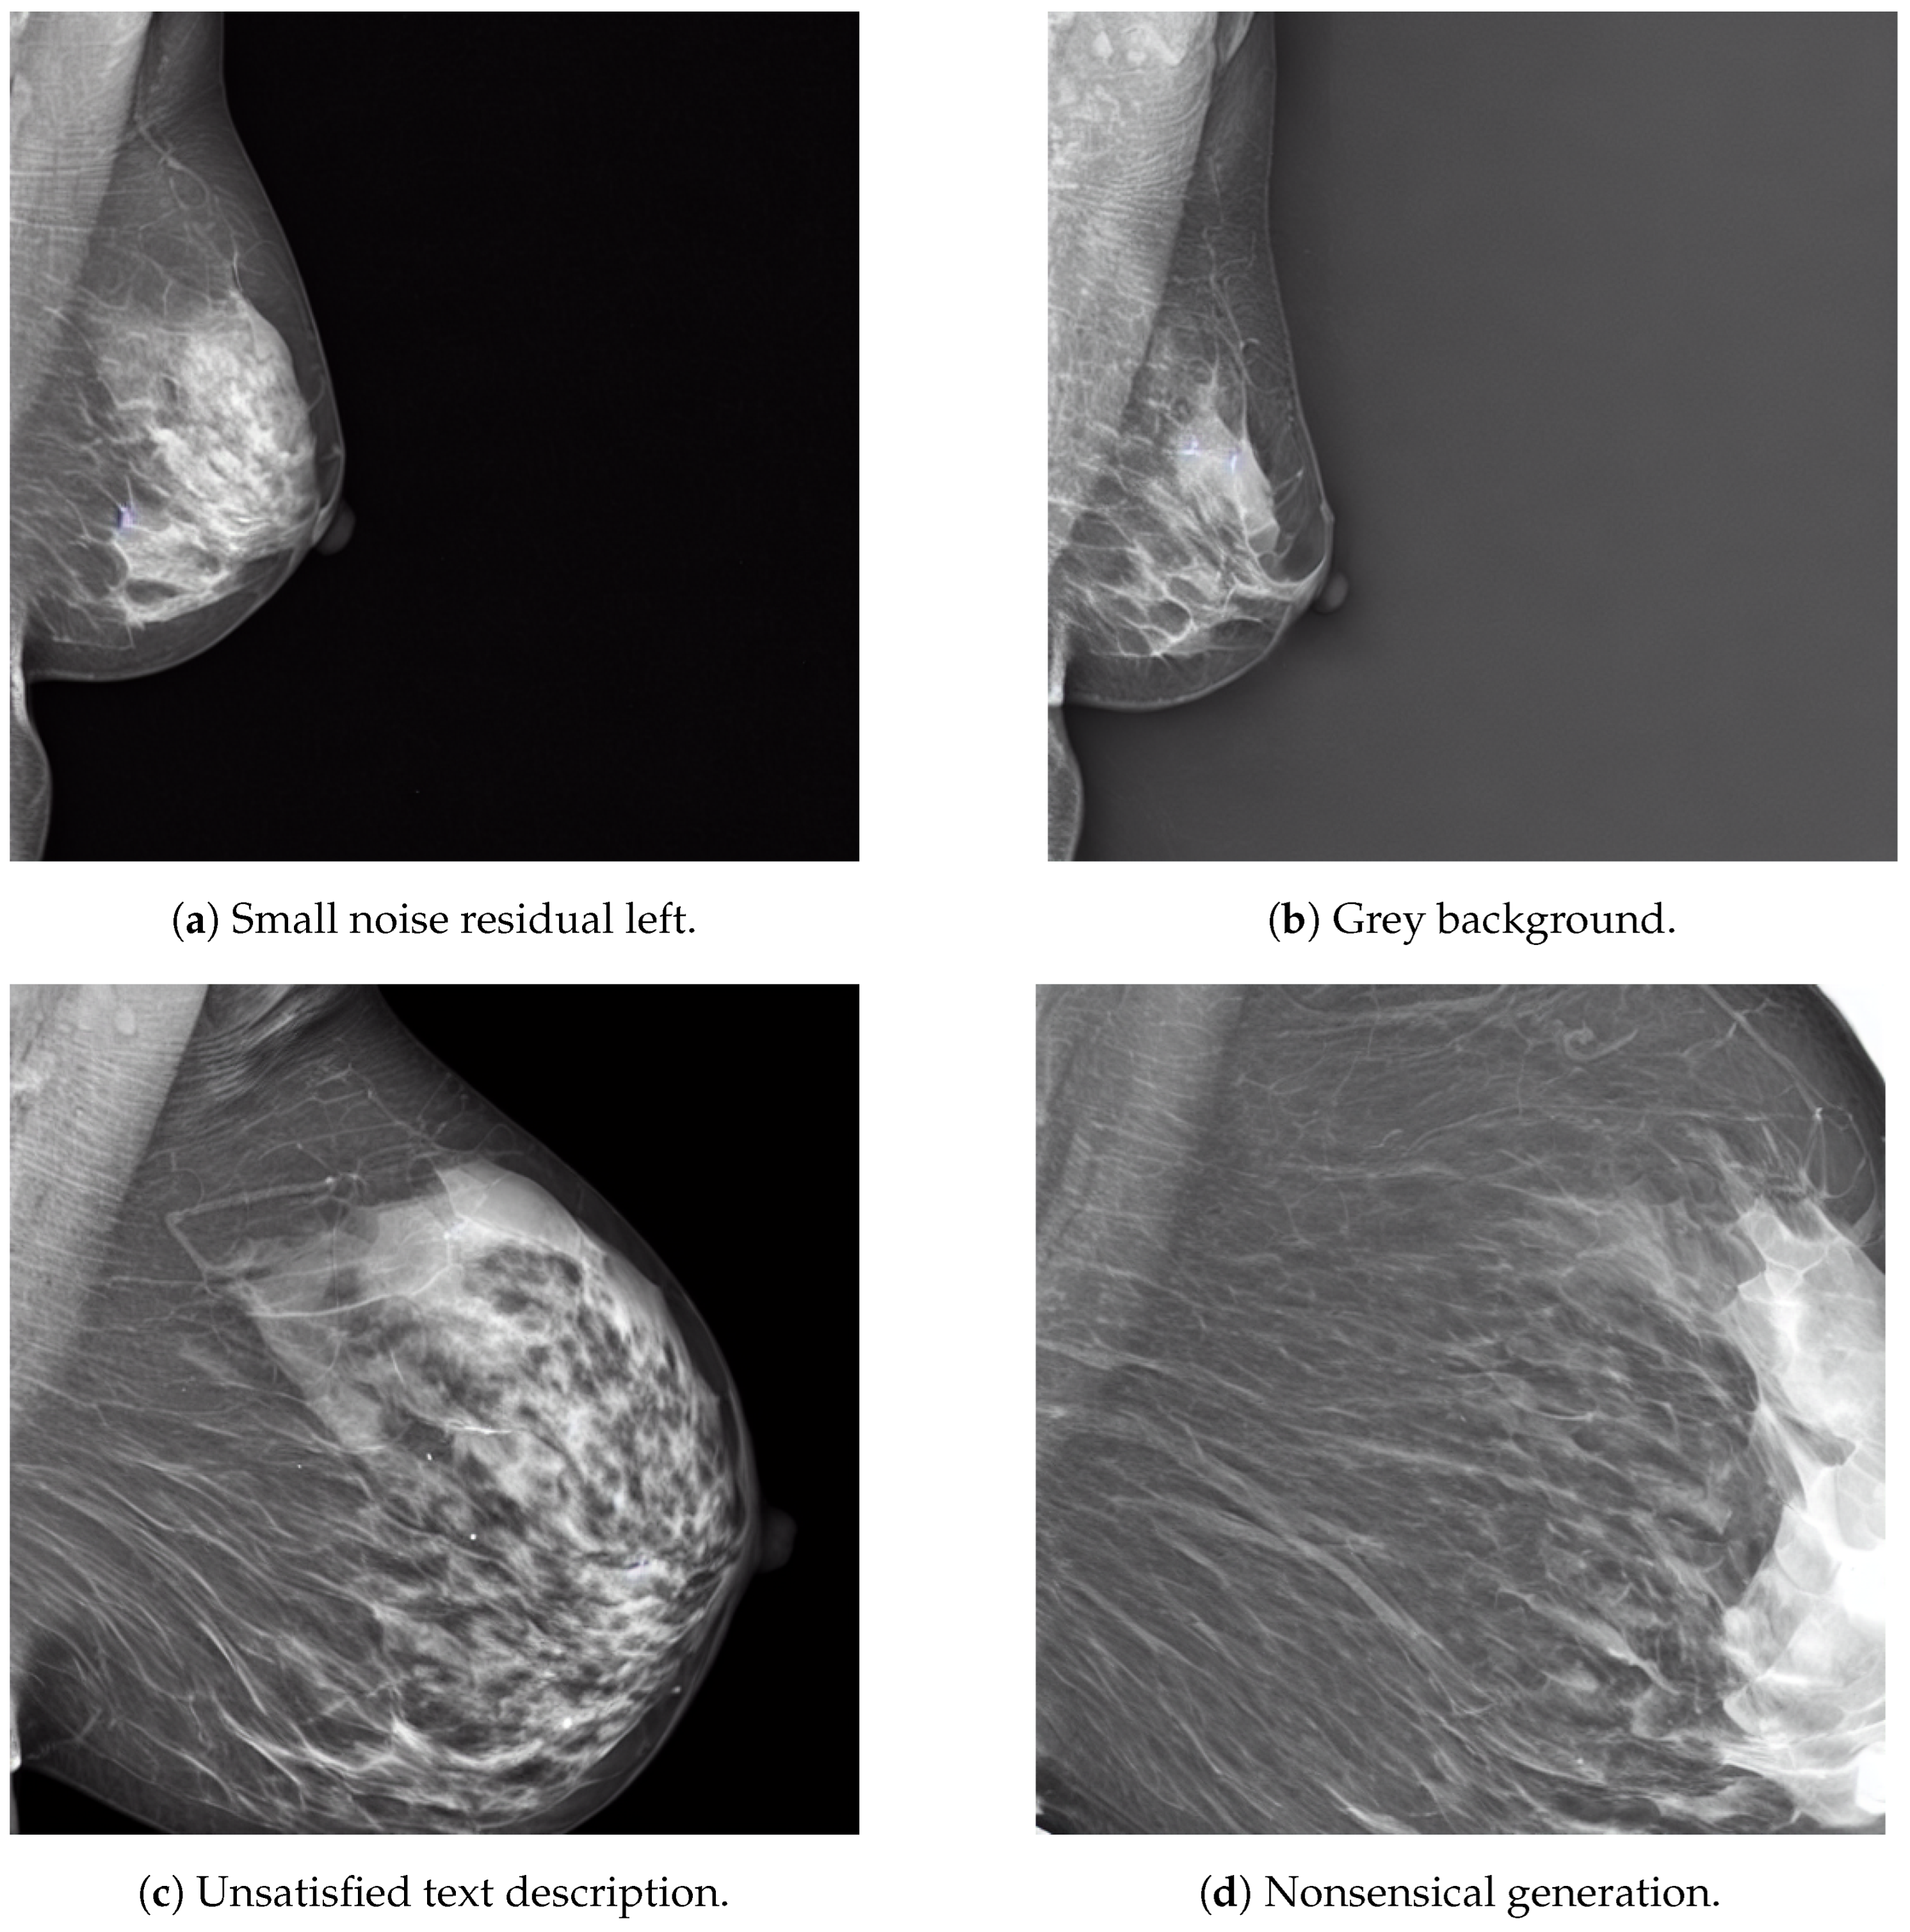

3.3. MAM-E Graphical User Interfaces